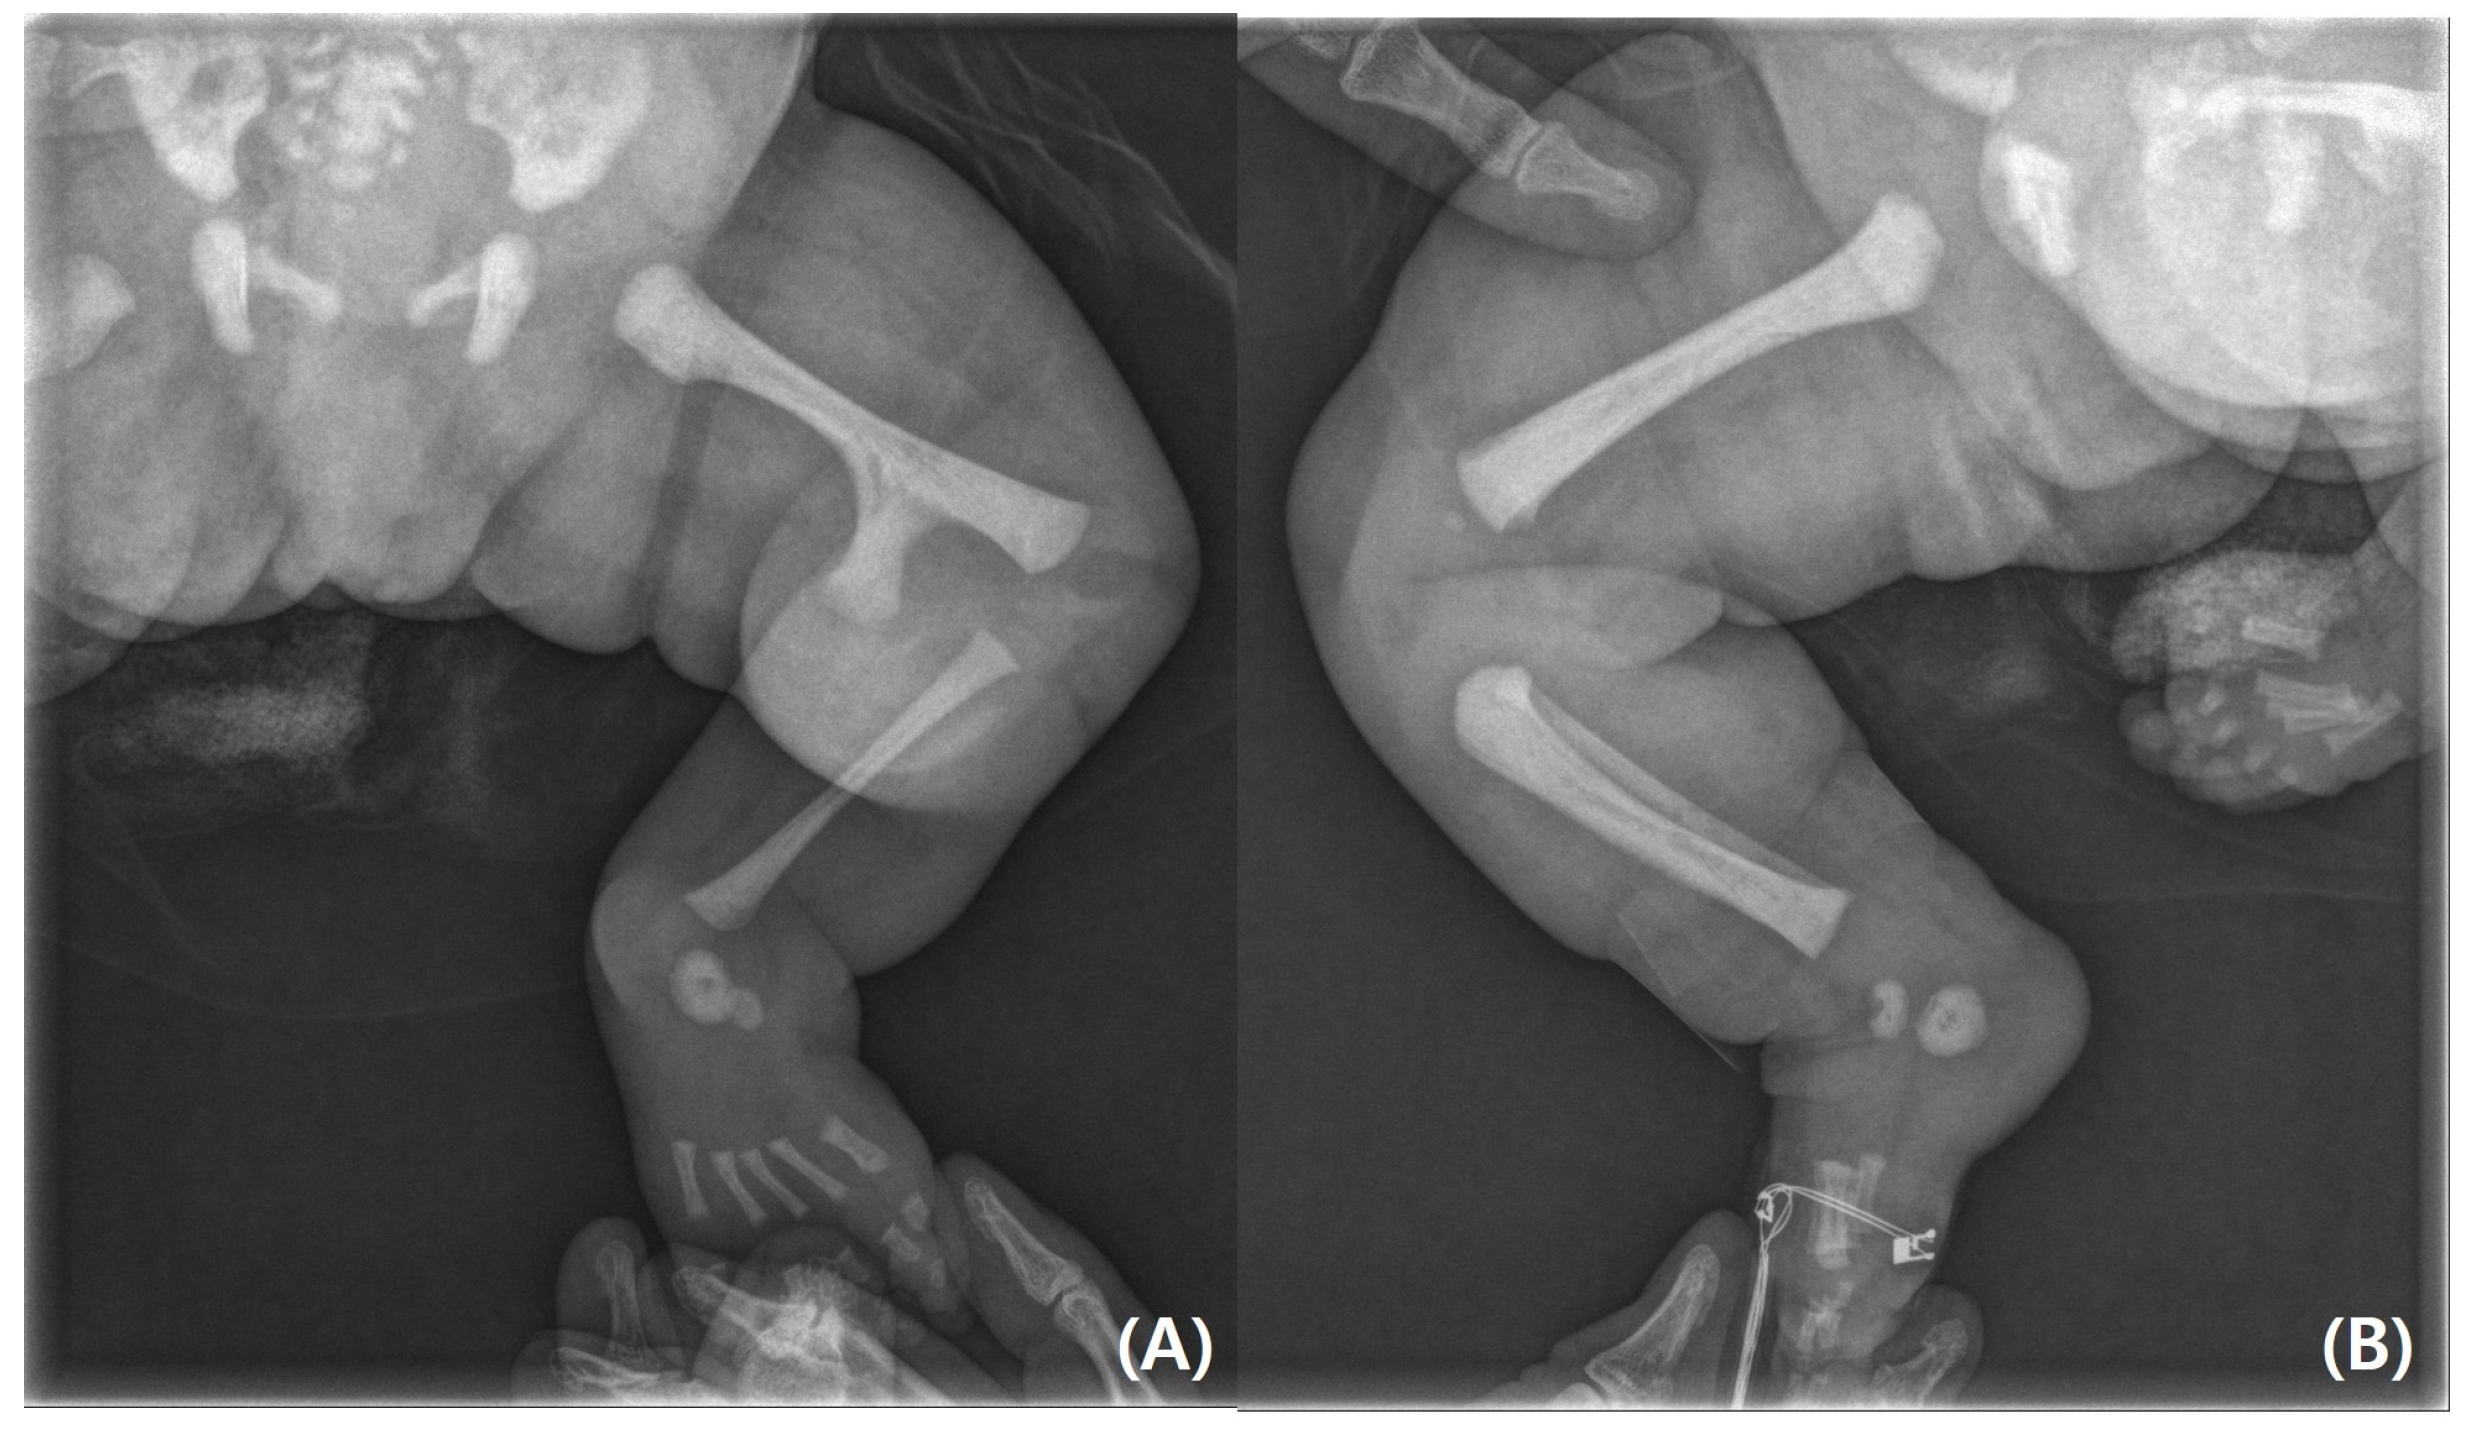

On physical examination, the infant’s left leg was shorter than the right leg, and her left foot had equinovarus (Figure 1). A large bony prominence was observed on the medial aspect of the left thigh. The left knee joint was unstable in all directions. The left fibula was palpable just lateral to the knee and ankle joints. The tibia, including the medial malleolus, was not palpable. The feet were grossly deformed because of equinovarus. Her upper extremities revealed contralateral tetradactylous ectodactyly, and the left side showed normal development with equal length and normal digits (Figure 2). A radiography examination of the lower extremities revealed the absence of the left tibia, a deformed left foot, and duplication of the distal left femur. No epiphyseal ossification was observed at the distal end of the left femur (Figure 3). Ultrasonography of the same leg confirmed weak quadriceps and undetectable patellar signals and additionally revealed a complete absence of any tibial anlage in the lower leg. Neurologically, the patient was intact, and on examination of her lower back, the gluteal cleft was midline with no dermatological anomalies on her lower back.

Figure 1. (A) Bony protuberance at the distal third of the anteromedial aspect of the left thigh. (B) Normally developed right lower limb.